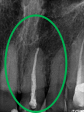

男性Uさん 60代(オールセラミック冠)

主訴

左下、歯がないところに歯をいれたい。

治療内容

残根のところは、根管治療をし、オールセラミック冠を被せました。歯がないところに1本インプラントを埋入しました。

所感

インプラントは、上の歯との噛み合わせの関係から、2本歯がないところに1本だけ埋入しました。

この症例は、3Dダイナミックナビゲーションシステム「Xガイド」を使った初めての症例です。当たり前のことですが、コンピューター上で立てた治療計画がそのまま再現され、とても気持ちが良かったです。

Xガイドは、CTスキャンの画像をもとに顎骨の形態や質、神経の位置などを把握しながら事前に立てた治療計画を正確に手術に再現できるようにサポートするナビゲーションシステムです。インプラントの埋入位置と角度は、「Xガイド」の3Dナビゲーションによって正確に把握されます。骨の中の神経や血管の位置をリアルタイムに確認しながら手術を実行できるため、より安全で精度の高いインプラント手術をすることができます。

オールセラミック冠1本:¥104,500×1本=¥104,500(税込)

インプラント1本:¥363,000×1本=¥363,000(税込)